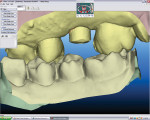

Patients were placed on a 1-week antibiotic regimen (amoxicillin), chlorhexidine 2 times daily, a low-dose steroid, and analgesics as needed. Strict oral hygiene instructions were given in writing and orally, and specific dietary protocols were given. After 14 days, the sutures were removed and each patient’s oral hygiene instructions were modified and the patients reinstructed. The implants were allowed to heal for approximately 3 to 5 months prior to definitive restoration. A digital scan of the BellaTek Encode healing abutment using the iTero intraoral scanner (Figure 1) was taken to include the opposing arch and 90-degree occlusal registration. All scanning data was sent to iTero to be processed and converted to standard triangulation language (STL) files in preparation for definitive abutment fabrication. The data was forwarded to the BellaTek™ Production Center at Biomet 3i, where the virtual BellaTek abutment was designed in preparation for the CAD/CAM milling process. For further modification and approval, a jpeg file can be sent to the restorative dentist to approve the design (eg, margin location) prior to final manufacturing.

In a sample case among the patients treated in this evaluation that depicts a typical application of the technology, a 28-year-old woman presented with recurrent caries associated with the mesial aspect of tooth No. A in the No. 4 position (Figure 2). The restorative dentist determined this tooth should not be retained and recommended extraction. The tooth was extracted approximately 6 months prior to implant placement. A 4.1/3.25-mm x 13-mm implant (NanoTite Certain, Biomet 3i) was placed in the No. 4 area with the aid of a surgical guide (Figure 3). The implant insertion torque value was set at 50 Ncm to achieve adequate primary stability. Primary stability was achieved and verified with the Osstell™ RFA device prior to the final restorative phase. The BellaTek Encode healing abutment was checked for mobility, and torque was verified at 20 Ncm (Figure 4 and Figure 5). A radiograph was taken for seating verification prior to the digital scan. A digital scan of the healing abutment using the iTero intraoral scanner was taken to include the opposing arch and 90-degree occlusal registration (Figure 6).